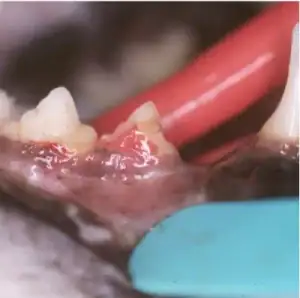

Cat with lower premolar tooth affected by tooth resorption of the crown. The gum is enlarged covering the cavity in the tooth